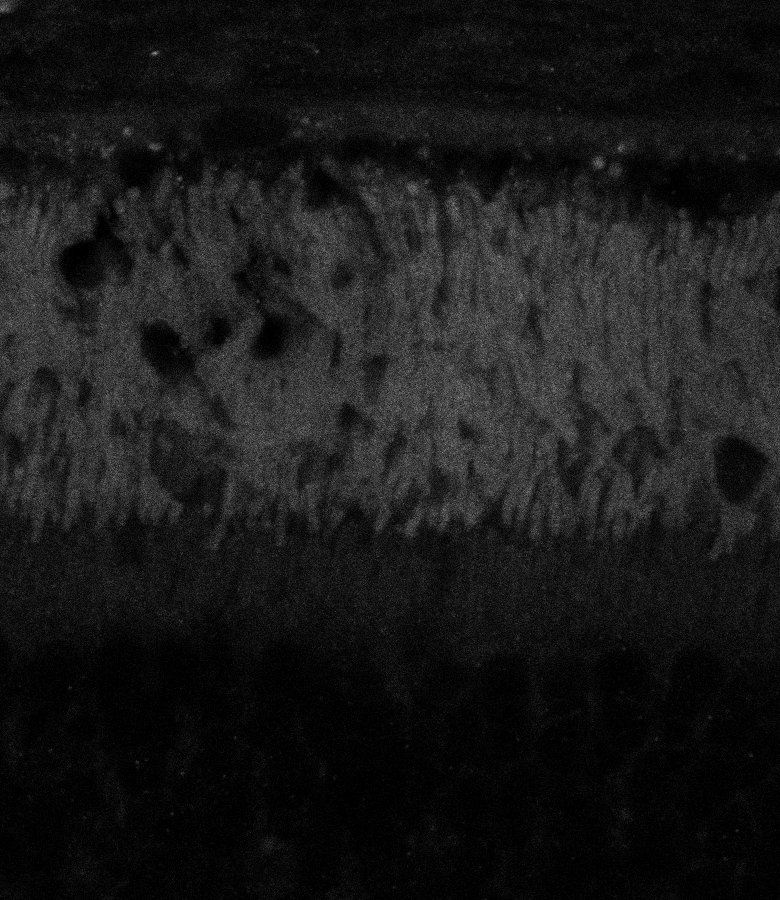

Healthy Retina

Unhealthy Retina